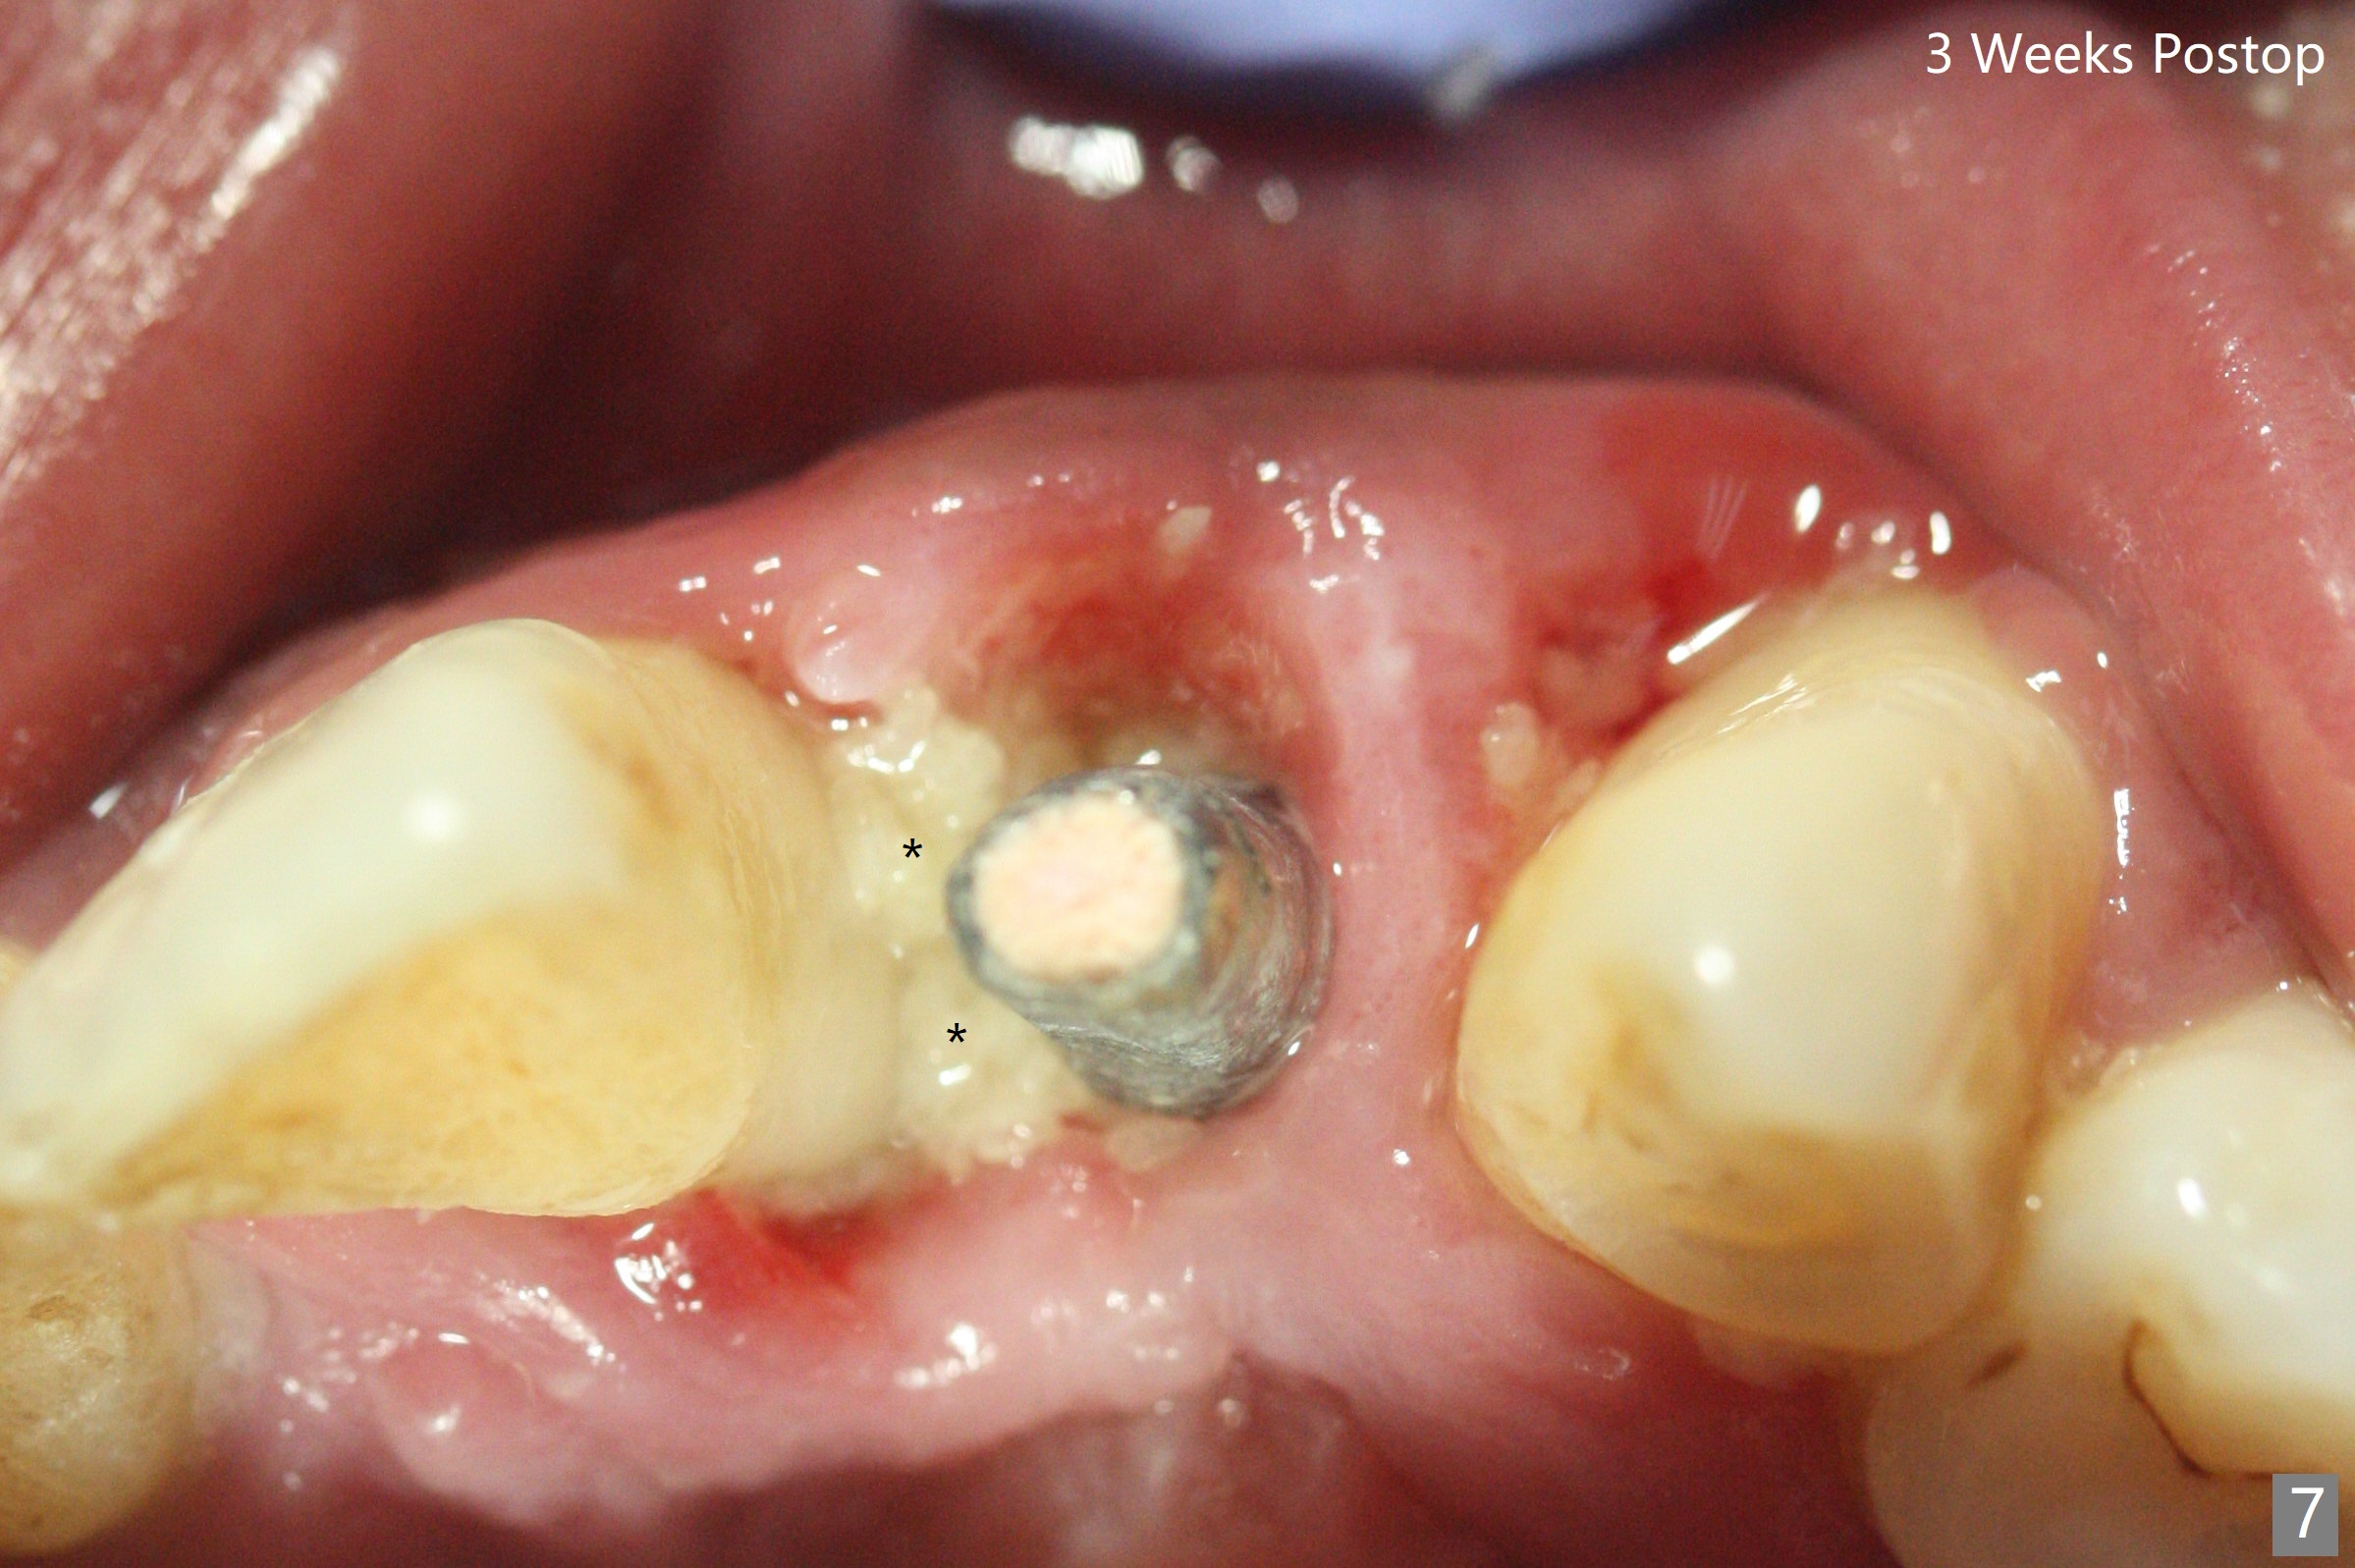

实验结果表明红管抽取上清液形成粘性骨块比白管快。左上二拔除,即刻徒手钻洞(图一),初步植入3.8x11.5毫米植体(图二),调整植体深度,然后放置直径4.5毫米长基台(图三,DIO UF; 牙龈厚度大于6毫米),最后填入大量粘性骨粉(图四,五 *),植体颊侧近中骨粉不足(图五 ^),之后再次充填骨粉。制作即刻修复物,颊侧瘘道和牙槽窝开口放置PRF膜。术后三周临时牙冠松动,取出后者,颊侧空间有两个区域:牙龈和骨粉(图六:白,黑星号)。由于脑部手术,术后接近一年病人回来取模。由于基台长,临时牙冠还没有脱落(图八)。牙龈袖正常(图九:*)。术后一年骨粉仍在植体,基台交界处(图十)。